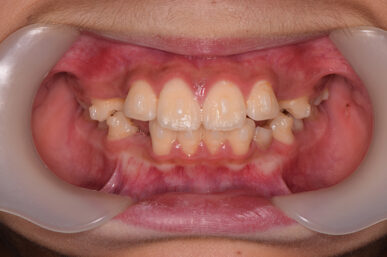

• After

治療の開始が遅く、犬歯と奥歯の生え代わりが始まっていましたが、床矯正より治療スピードが早いアライナー矯正を使用して、犬歯のスペースをとても短期間に作ることができました。八重歯を防げましたので固定式の装置は必要なくなりました。永久歯がすべて生えるまでは予防歯科で歯の生え代わりと機能を管理します。